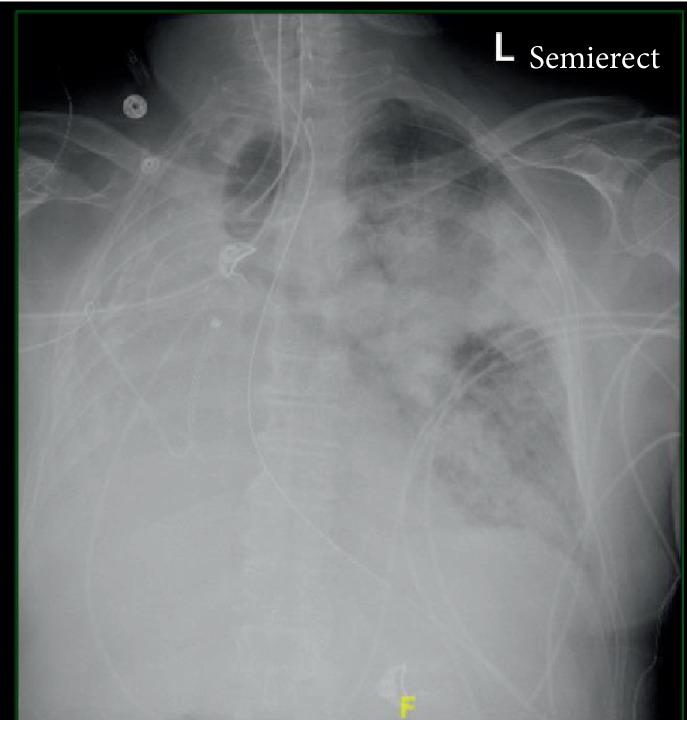

Postpneumonectomy syndrome involves mediastinal shift causing dynamic airway obstruction via compression of the main bronchus and distal trachea. A few case reports describe the development of ARDS in patients with postpneumonectomy syndrome. Reeb et al. (2017) describe the mortality of postpneumonectomy ARDS anywhere from 33% to 88%. One may encounter difficulty in intubation and ventilation as parameters based on ideal body weight may not apply. Prone positioning ventilation and ECMO have been successfully used in isolated cases. We present such a case and highlight challenges in management. A 70-year-old male Vietnam veteran with remote history of right pneumonectomy thirty years prior presented with fever, cough, and dyspnea. Physical exam was significant for T 36.3°C, BP 162/73, heart rate 145 BPM, RR 22 breaths/minute, ht. 1.72 m, and wt. 78 kg, with transmitted right lung sounds and rhonchi on the left. Labs showed WBC 23.92/nL and procalcitonin 0.84 ng/mL. CXR showed left infiltrate and opacification of right hemithorax with right mediastinal shift. EKG showed atrial fibrillation. He was started on broad spectrum antibiotics for pneumonia, but deteriorated, and was intubated for respiratory distress from ARDS. Vasopressors were initiated for shock. Given the history of pneumonectomy, he was initially ventilated with lower tidal volumes (320 mL). However, incremental changes were made to tidal volumes, and ETT was repositioned several times for hypoxia. Epoprostenol and cisatracurium were also initiated. Positional changes would lead to sudden desaturation; hence, prone positioning ventilation was not done. He was not considered for ECMO due to his pneumonectomy status. Unfortunately, his condition worsened progressively and he expired. The guidelines for ARDS are well established. However, postpneumonectomy patients are unique as seen in our patient. It is unclear whether an endobronchial tube advanced into the left bronchus could have helped difficult airway management resulting from suspected postpneumonectomy syndrome as suggested by CXR. Higher tidal volumes were also unsuccessful in alleviating hypoxia and led to persistently elevated plateau pressures and driving pressures as high as 23, which was inconsistent with our goal of lung protective ventilation. Few case reports describe the successful use of prone positioning ventilation or ECMO in postpneumonectomy patients with ARDS. Although not well studied, low tidal volumes supported with ECMO may have been a favorable strategy for our patient.

肺切除术后综合征包括纵隔移位,通过压迫主支气管和远端气管导致动态气道阻塞。少数病例报告描述了肺切除术后综合征患者发生急性呼吸窘迫综合征(ARDS)的情况。里布等人(2017年)描述了肺切除术后ARDS的死亡率在33%至88%之间。由于基于理想体重的参数可能不适用,在插管和通气方面可能会遇到困难。俯卧位通气和体外膜肺氧合(ECMO)已在个别病例中成功应用。我们介绍这样一个病例,并强调管理中的挑战。一名70岁的男性越南退伍军人,30年前有右肺切除史,现出现发热、咳嗽和呼吸困难。体格检查显示体温36.3°C,血压162/73,心率145次/分钟,呼吸频率22次/分钟,身高1.72米,体重78公斤,右肺有传导音,左肺有干啰音。实验室检查显示白细胞计数23.92/微升,降钙素原0.84纳克/毫升。胸部X线片显示左肺浸润,右半胸混浊,伴有右纵隔移位。心电图显示心房颤动。他因肺炎开始使用广谱抗生素,但病情恶化,因ARDS导致呼吸窘迫而插管。因休克开始使用血管活性药物。鉴于有肺切除史,最初给予较低潮气量(320毫升)通气。然而,逐渐增加潮气量,并多次重新调整气管内插管位置以改善缺氧。还开始使用依前列醇和顺式阿曲库铵。体位改变会导致突然的血氧饱和度下降;因此,未进行俯卧位通气。由于他的肺切除状态,未考虑使用ECMO。不幸的是,他的病情逐渐恶化,最终死亡。ARDS的指南已经很完善。然而,正如我们的患者所示,肺切除术后患者有其独特之处。正如胸部X线片所示,将支气管内导管推进左支气管是否有助于处理疑似肺切除术后综合征导致的困难气道管理尚不清楚。较高的潮气量也未能缓解缺氧,导致平台压持续升高,驱动压高达23,这与我们的肺保护性通气目标不一致。少数病例报告描述了在肺切除术后ARDS患者中成功使用俯卧位通气或ECMO的情况。虽然研究不足,但对于我们的患者,用ECMO支持的低潮气量可能是一种有利的策略。